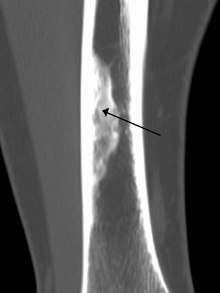

An ossified non-ossifying fibroma on CT

A nonossifying fibroma (also called fibroxanthoma) is a fibrous bone lesion that is usually asymptomatic and discovered as an incidental finding on x-ray. It is the most common benign bone tumor in children and adolescents. However, it is controversial whether it represents a true neoplasm or rather a developmental disorder of growing bone. Radiographically, the tumor presents as a well marginated radiolucent lesion, with a distinct multilocular appearance. These foci consist of collagen rich connective tissue, fibroblasts, histiocytes and osteoclasts. They originate from the growth plate, and are located in adjacent parts of the metaphysis and diaphysis of long bones, most often of the legs. No treatment is needed in asymptomatic patients and spontaneous remission with replacement by bone tissue is to be expected.